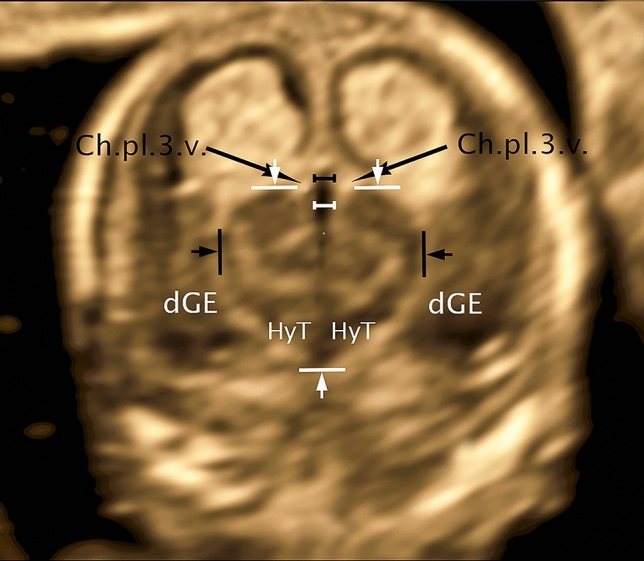

The presentation of the thalamus in the selected coronal plane dorsal to the hemispheric peduncle reveals a clear outline (Fig. 4). Cranially, the thalamus shows a strong convex bulge into the interhemispheric fissure on either side of cavum velum interpositum (CVI). The lateral border, also convex shaped, as an expression of the pronounced growth separates well from the adjacent hyperechogenic structures of Plexus choroideus of the lateral ventricle. Caudally thalamus, without a distinct limit, merges into the hypothalamus, whose caudal boundary is the hyperechogenic subarachnoid space of the base of the scull. Lateral to the narrow hyperechoic fissure, choroid plexus of the lateral ventricle, caudal ganglionic eminence presents, well demarcated from the surrounding cerebral wall. Furthermore, the full craniocaudal extent of the 3rd ventricle is well visualized, beginning with its cranial portion CVI, extending above the tela choroidea of the pl. ch.3.v into the interhemispheric fissure, showing a well-depicted lumen. Caudally the 3.v presents about the same width of the lumen becoming a fissure after a short distance reaching almost to the end of the hypothalamus. Nucleus arcuatus closes as a narrow tissue bridge, caudally adjacent to the gap of 3.v.

Fig. 4.

CRL 63.3 mm, coronar: Ch.pl.3.v.—choroid plexus third ventricle; dGE—dorsal ganglionic eminence; HyT—hypothalamus; distance white—distance third ventricle lateral; distance black—distance cavum velum interpositum lateral; distance arrows black—distance thalamus lat; distance arrows white—distance thalamus/hypothalamus craniocaudal

For measurement of thalamus and hypothalamus craniocaudal in the transthalamic coronar plane, a line was placed at the upper edge of the two cranial protrusions of thalamus right and left of the midline and defined as the cranial border, whereas the blunt caudal end of hypothalamus was defined as the caudal border, for the measurement of thalamus lateral the maximum lateral width was used (Fig. 4).

For the measurement of 3.v we also used this plane, measuring the maximum distance below the choroid plexus of the 3rd ventricle adjacent to the cranial edge of the thalamus (below CVI) (Fig. 4).